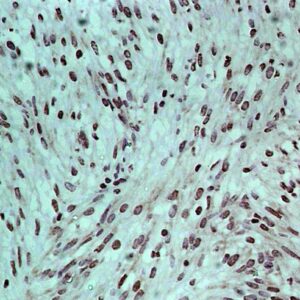

BioGenex has pioneered the development of miRNA research and diagnostics tools with leading-edge products. Currently, we offer over 240 ready-to-use (RTU) Super Sensitive™ Nucleic Acid (SSNA) miRNA ISH probes for accurate and early tumor diagnosis. These probes are sensitive enough to detect low-abundant miRNA(s) that are often required to identify biomarkers. They have a high melting temperature enabling stringent washes to remove non-specific binding. BioGenex miRNA probes are dual-end labeled with an anti-fluorophore to amplify the signal and yield clean and intense staining.